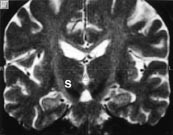

Erkendelse af den med årene ofte svigtende effekt af levodopabehandling af Parkinsons sygdom (PS) har været medvirkende til at genoplive interessen for Parkinsonkirurgien. Den forbedrede billeddiagnostiske teknik i form af CT og MR-scanning kombineret med stereotaktiske kirurgiske principper og computerteknik til beregning af målområdet har øget mulighederne for en meget præcis placering af læsionen/elektroden og tillader inddragelse af anatomisk mindre målområder som fx nucleus subthalamicus (1, se også senere og fig 1 og 2). Formålet med denne artikel er at beskrive aktuelle kirurgiske behandlingsformer af PS og begrunde valget af metode i Danmark i dag.

De i 1950’erne og 1960’erne anvendte operationer med læsion, dvs. elektrokoagulation i globus pallidus interna (GPi) (pallidotomi) rettet mod modsidige Parkinsonsymptomer og elektrokoagulation i thalamus (talamotomi) rettet mod modsidig tremor, søges i dag afløst af elektrisk stimulation (neuroinhibition) lokalt i områderne via en implanteret elektrode (fig 3).